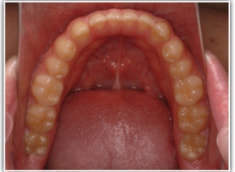

開咬(かいこう:オープンバイト)ケース

治療法:表の矯正(T21ブラケット)

(インプラントアンカーや外科矯正は行わず、エラスティックと機能訓練のみ)

治療前

治療後(2年2ヶ月後)